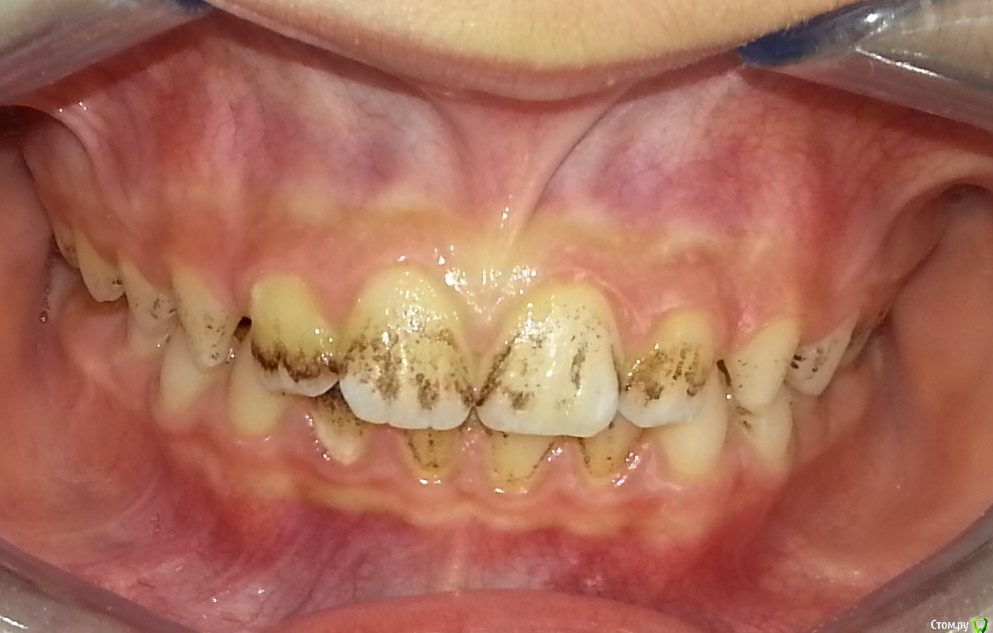

Nitrino1 Опубликовано 6 февраля, 2017 Поделиться Опубликовано 6 февраля, 2017 Здравствуйте коллеги, помогите с уточнением диагноза) Я не детский стоматолог, мамаша принесла ребенка заодно проконсультировать по поводу налета, посмотрел сфоткал) Первое что пришло на ум это налет Пристли)) Хотел уточнить) Жалоб нет, только эстетика..Убирали налет у стоматолога, через месяц все заново появилось.Буду благодарен если уточните как добиться постоянного эффекта.Ребенку 10 лет, мальчик Ссылка на комментарий

Петренкуся Опубликовано 7 февраля, 2017 Поделиться Опубликовано 7 февраля, 2017 Можно: 1- проверить кровь на избыток железа,2- может быть признаком дисбактериоза ( в любом случае придётся постоянно чистить ). Годам к 17-19 у большинства уходит, но у меня есть постоянная пациентка, ей уже 36 лет,чистим раз в полгода много - много лет. Правда, обследование не проводили, ее устраивает регулярная гигиена. Ссылка на комментарий

Тань Опубликовано 7 февраля, 2017 Поделиться Опубликовано 7 февраля, 2017 Почистить содой и назначить пасту с содержанием цинка, например "Бирепайр Тотал" или "Сплат Арктикум" Ссылка на комментарий

Тань Опубликовано 9 февраля, 2017 Поделиться Опубликовано 9 февраля, 2017 почему именно содой (она же травмирует эмаль), и почему именно с содержанием цинка?Потому, что только сода его счищает до конца, а цинк обладает антисептическим и антибактериальным действием, но не таким агрессивным как хлоргексидин. У моих пациентов никакого повреждления эмали не наблюдалось пока, наоборот, гладкая, отполированная поверхность, но у меня сода в "Аквакат" на самой маленькой силе подачи порошка и паста "Клиник Керр" с резиновыми чашечками "Керр" и завершаю "Эмаль Герметизирующий Ликвид" 5 минут по инструкции, а пасту с цинком стала назначать по совету пародонтолога. Но конечно же налет Пристли возвращается,но меньше, на 3 месяца хватает.. Попробуйте. Ссылка на комментарий